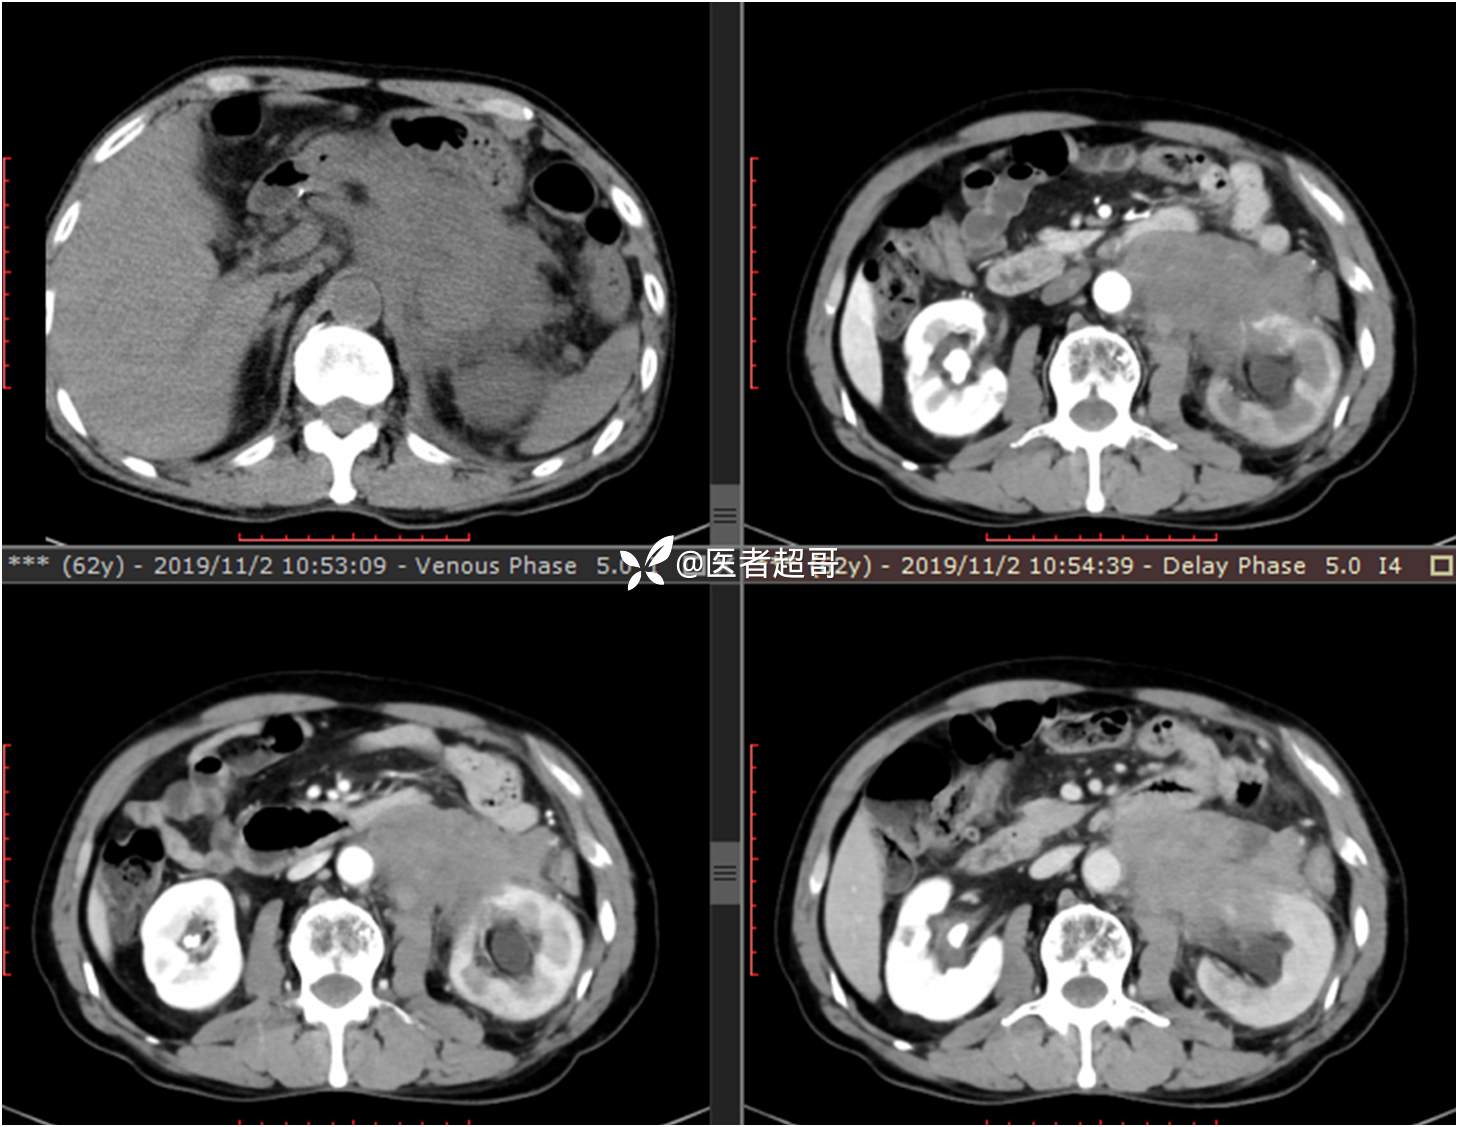

现病史:患者于1月前无明显原因及诱因出现左上腹部疼痛,为间断性疼痛,无恶心、呕吐,无寒战、高热,无腹胀、腹泻等伴随症状,在外未行特殊处理,患者于1周前自觉疼痛加重,为求诊治患者曾就诊于市东城医院,行全腹部强化CT提示:左肾上腺区肿块,符合恶性肿瘤侵犯左肾、胰腺及腹膜后大血管CT表现,行保守治疗,症状缓解,今患者为求进一步诊治,来我院就诊,行腹膜后占位穿刺活检病理提示:(腹膜后占位穿刺)小细胞背景内见细胞浆红染的神经节样细胞,建议到病理科加做免疫组化进一步明确诊断,遂以“腹膜后肿物”收入院,患者自发病以来,神志清,精神可,饮食、睡眠差,大小便正常,体重未见明显改变。